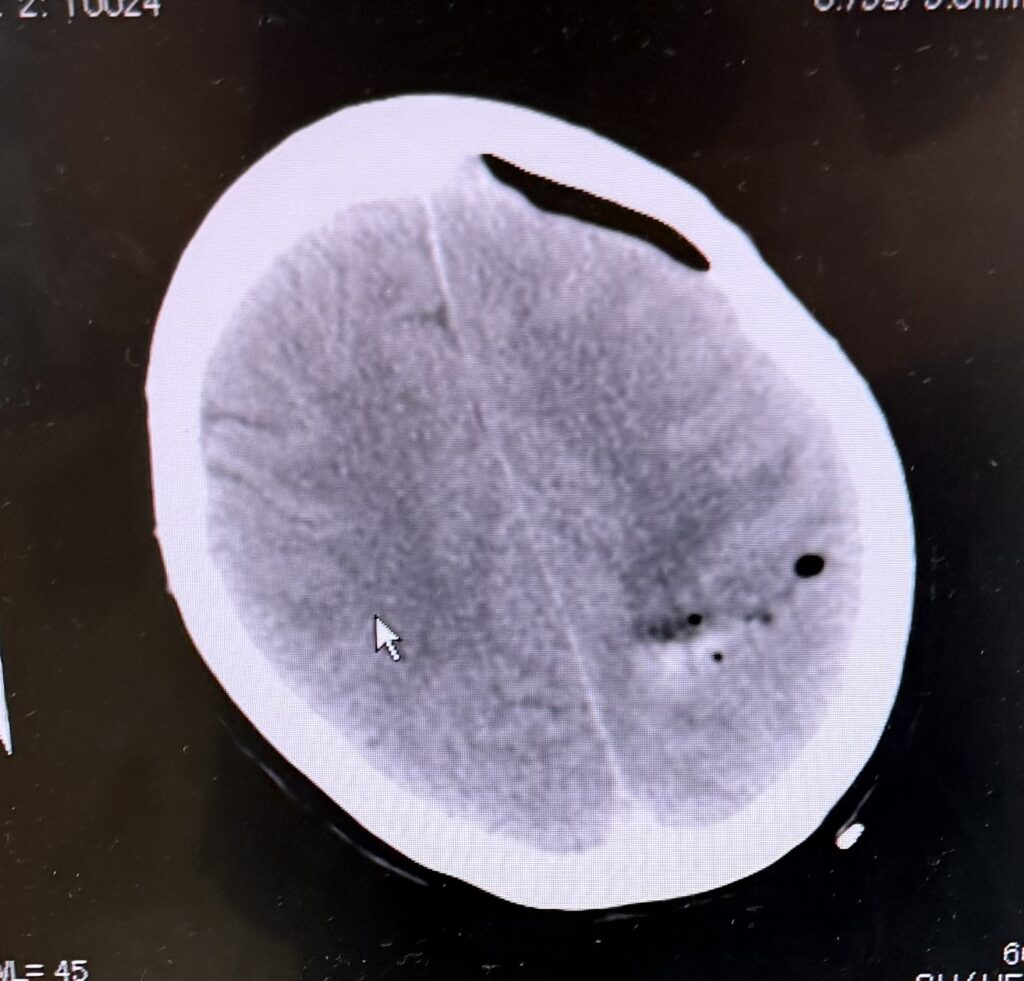

術前

画像は診療後に夜の緊急手術で内視鏡下血腫除去をした症例の写真です(局所麻酔、1時間で実施)。